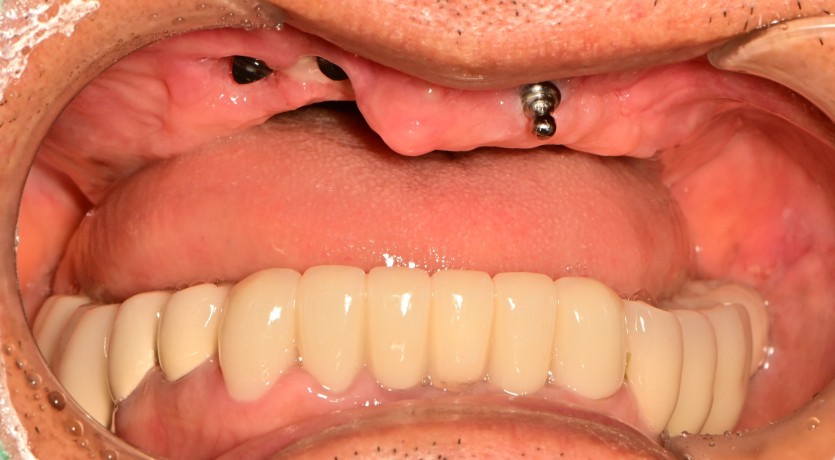

만 73세 상악 전체 임플란트 증례(기존 임플란트 제거)

상악 전체 임플란트 증례입니다.

9개의 임플란트로 완성하였습니다.